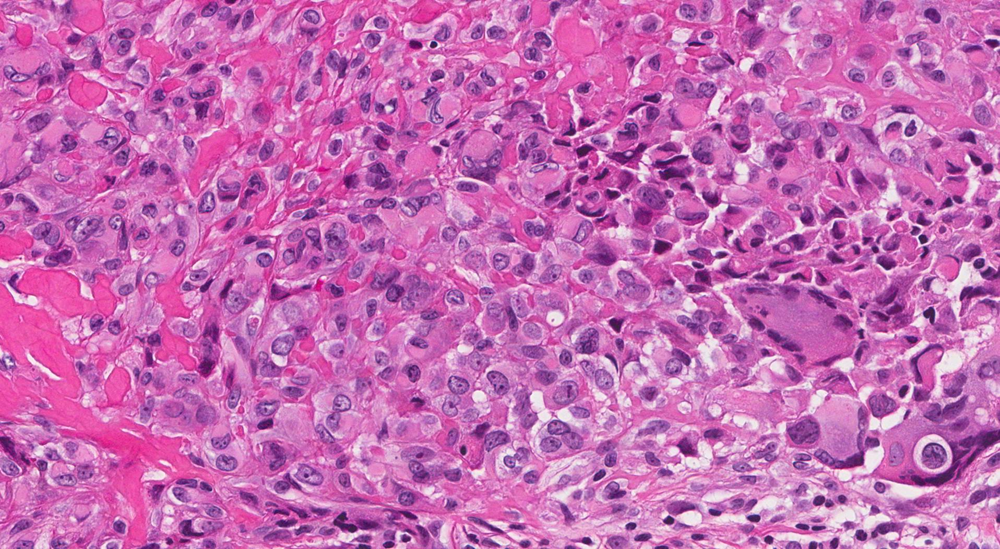

Do đặc điểm hình thái và miễn dịch phức tạp, Sarcoma mô bào dễ bị nhầm với các loại u hoặc viêm khác như lymphoma, ung thư biểu mô kém biệt hóa, u hắc tố hoặc các sarcoma khác (Hình minh họa/Internet)

Bác sĩ Vũ Xuân Ngọc, Phụ trách khoa Giải phẫu bệnh học, cho biết Sarcoma mô bào là một rối loạn mô bào rất hiếm, liên quan đến các bệnh lý ác tính về máu và đôi khi kèm theo u tế bào mầm. Tỷ lệ mắc chỉ khoảng 0,17 ca trên 1 triệu người. Do đặc điểm hình thái và miễn dịch phức tạp, bệnh dễ bị nhầm với các loại u hoặc viêm khác như lymphoma, ung thư biểu mô kém biệt hóa, u hắc tố hoặc các sarcoma khác. Việc chẩn đoán đòi hỏi sự tỉ mỉ để loại trừ các khả năng khác.